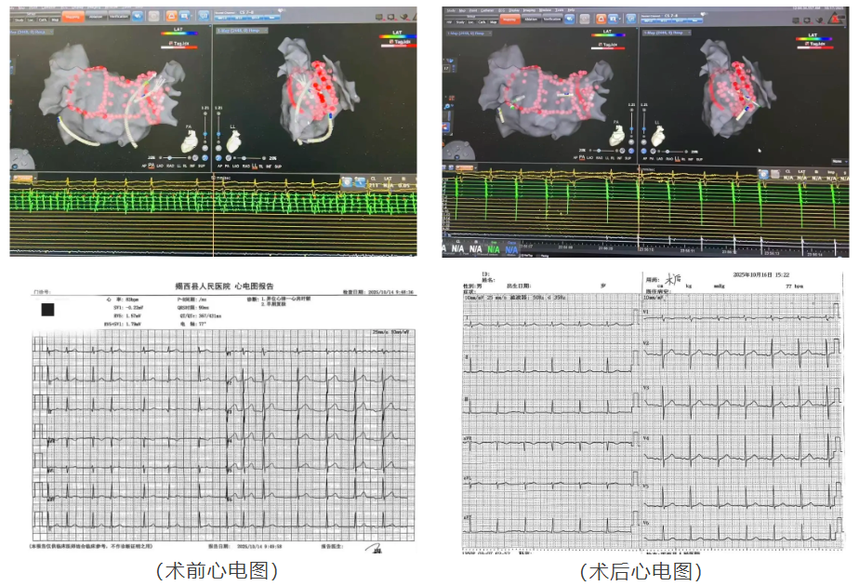

针对李先生的复杂病情,副院长兼心血管内科主任张优惕迅速组织医师团队开展病例讨论,为患者制定治疗方案。 暂时性处置:予西地兰控制心室率、利伐沙班抗凝,控制患者症状;多学科联合评估:NT-proBNP 1753.9pg/ml,甲状腺功能未见异常,心脏彩超显示左房未见明显扩大(LA 34mm),但射血分数保持正常(EF58%);复查冠脉造影:回旋支中段局限性狭窄50%,前降支中段支架未见明显狭窄,排除缺血性心脏病。 传统药物治疗仅能 “治标”,无法根治房颤,而射频消融术才是实现 “治本” 的关键。结合李先生的病情复杂性与个体差异,张优惕副院长果断决定为其实施房颤射频消融术。

手术当天,在汕头大学医学院第一附属医院萧钟波教授精湛技术的指导下,我院心血管内科团队全神贯注,开始了这场与“心乱”的较量。心内电极导管在萧钟波教授的操控下,小心翼翼地在心脏内行进,修复着心脏的节律。医护人员紧盯监测仪器,密切关注着心脏电活动的变化。当最后一个颤动波在屏幕上消失,窦性心律稳定恢复的瞬间让所有人振奋——这标志着持续性房颤射频消融术获得成功!

此例手术成功的背后,是多学科协作的力量:超声科即时评估心脏结构;放射科辅助左房CTA(排除左心耳血栓);心血管内科医生团队优化抗凝、抗心律失常和降压方案,将风险降至最低;护理团队实施房颤专病护理常规,严格监测术后并发症,目前患者恢复良好,已顺利出院,后期随访患者心率恢复正常。